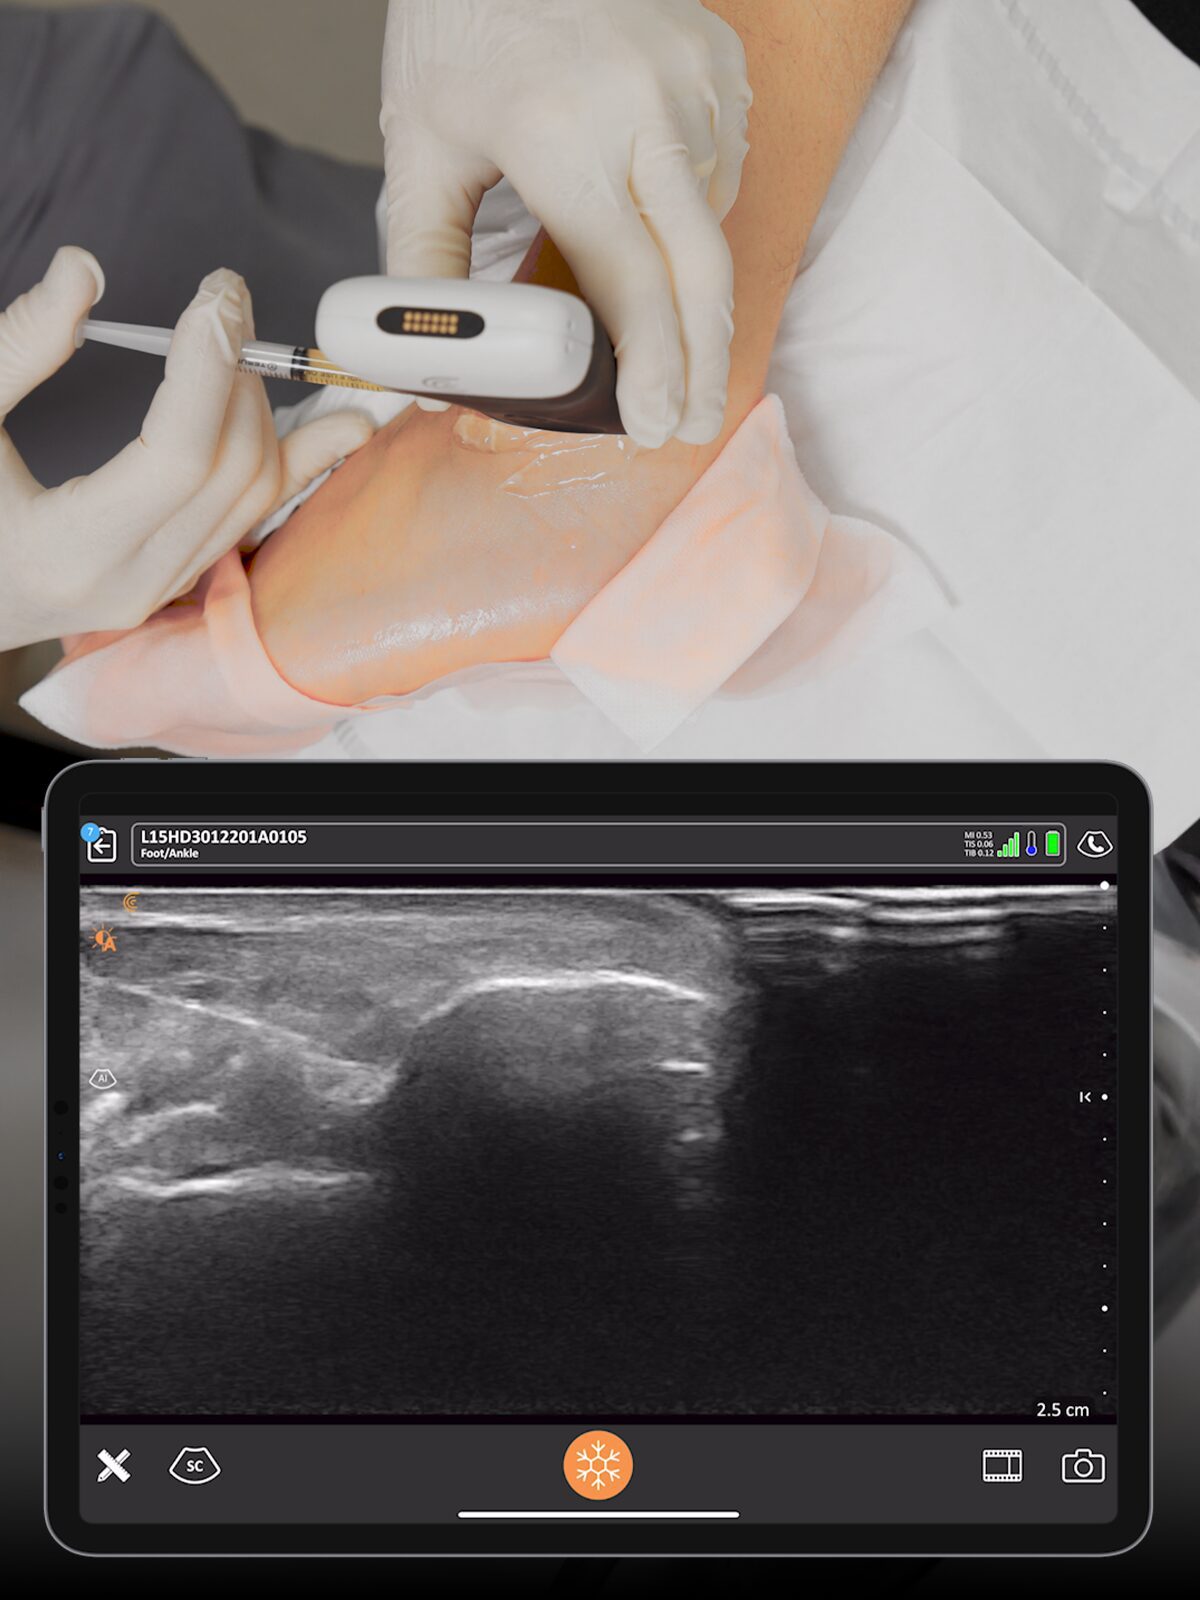

Precise Injections. Better Results.

Visualize targets in real time for precise nerve blocks and corticosteroid injections—reducing injectate volumes and boosting safety, confidence, and patient outcomes.